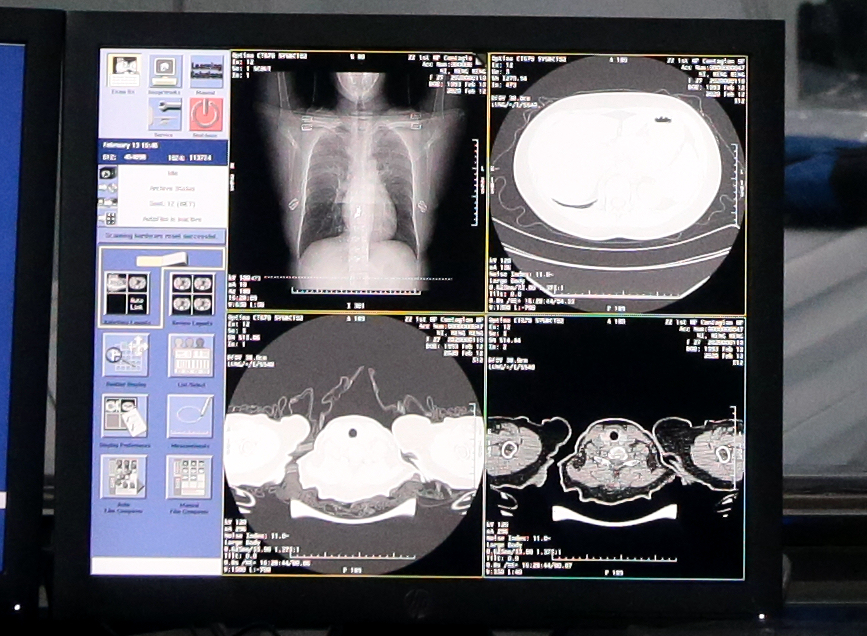

AI诊断系统在抗击新型冠状肺炎疫情领域又传来好消息,据阿里达摩院透露,达摩院最新AI算法诊断技术可在20秒内对新冠疑似案例CT影像做出判读,分析结果准确率达到96%。该算法辅助诊断技术将在2月16日起在河南郑州小汤山启用。

根据国家卫健委公布的诊疗方案第五版,临床诊断无需依赖核酸检测结果,CT影像临床诊断结果可作为新冠肺炎病例判断的标准。新冠肺炎患者的CT胸片的影像特征表现为单肺或双肺多发、斑片状或节段性磨玻璃密度影等细微变化。一位新冠肺炎病人的CT影像大概在300张左右,这给医生临床诊断带来巨大压力,医生对一个病例的CT影像肉眼分析耗时大约为5-15分钟。

达摩院医疗AI团队基于当前最新的诊疗方案、钟南山等多个权威团队发表的关于新冠肺炎患者临床特征的论文,与多家机构合作,基于5000多个病例的CT影像样本数据,学习训练样本的病灶纹理,研发了全新的AI算法模型。通过NLP自然语言处理回顾性数据、使用CNN卷积神经网络训练CT影像的识别网络,AI可以快速鉴别新冠肺炎影像与普通病毒性肺炎影像的区别,最终识别准确率高达96%。AI每识别一个病例平均只需要不到20秒,大大提高诊断效率,减轻医生压力。